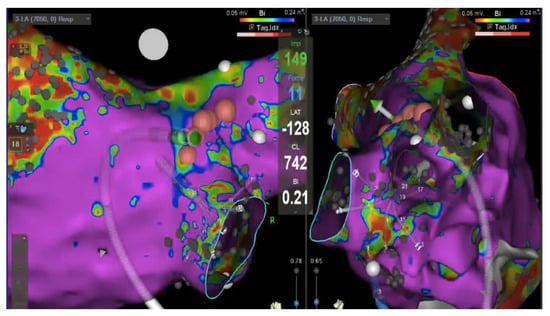

5. CMR-Guided Ablation

- The DICOM images are imported in a dedicated workstation, and they are segmented;

- During the procedure the LA is electroanatomically mapped using a dedicated catheter;

- The anatomic CMR map is merged with the electroanatomic one to obtain a hybrid map; and

- Finally, the ablation catheter is navigated in the LA using a hybrid map [72].